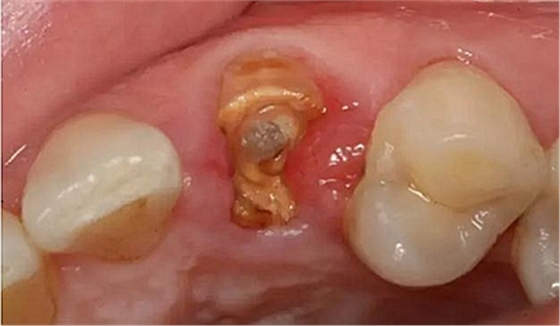

病例一 女性,20歲,大學(xué)生,要求補牙,檢查口內(nèi)可見A6大面積缺損,近中牙齦息肉,拍X片,根管充填物略差,但根周未見明顯陰影,口內(nèi)檢查無叩痛。建議患者冠延長手術(shù)+高嵌體修復(fù)。

患牙遠(yuǎn)中邊緣嵴完整,強度沒有降低,故擬保留遠(yuǎn)中邊緣嵴,高嵌體修復(fù)。首先去除腐質(zhì)及原墊底材料,流體樹脂+3M Z350XT樹脂墊底。局麻下行冠延長手術(shù)。在此需要提及個人的一個觀點。冠延長手術(shù)原則上要求3-6個月以上才能永久修復(fù)。但是個人喜歡后牙肩臺建立在齦上,所以修復(fù)后的修復(fù)體邊緣位于牙齦上方1mm,對牙周的愈合影響較小(如果為齦下邊緣則要慎重),故該患者術(shù)中按照齦上邊緣的設(shè)計進行冠延長手術(shù)。以下為術(shù)中: